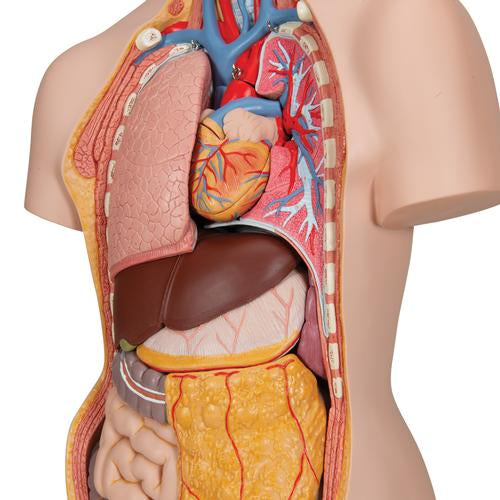

This meticulously crafted torso is expertly hand-painted with precision and made from high-quality plastic. All 3B torsos are designed and produced in Germany. This unisex human torso model features a distinctive open neck and back section extending from the cerebellum to the coccyx. It accurately depicts vertebrae, intervertebral discs, spinal cord, spinal nerves, vertebral arteries, and numerous other components in this vibrant representation of human anatomy. This human torso model includes the following detachable parts and organs:

- Removable 7th thoracic vertebra

- 6-part head

- Pair of lungs

- 2-part heart

- Stomach

- Liver with gall bladder

- 2-part intestinal tract

- Front section of kidney

- Front section of urinary bladder

Each organ in this human torso is hand-painted to ensure a high-quality product. This exceptional educational tool for human anatomy simplifies learning the placement of human organs. It is a